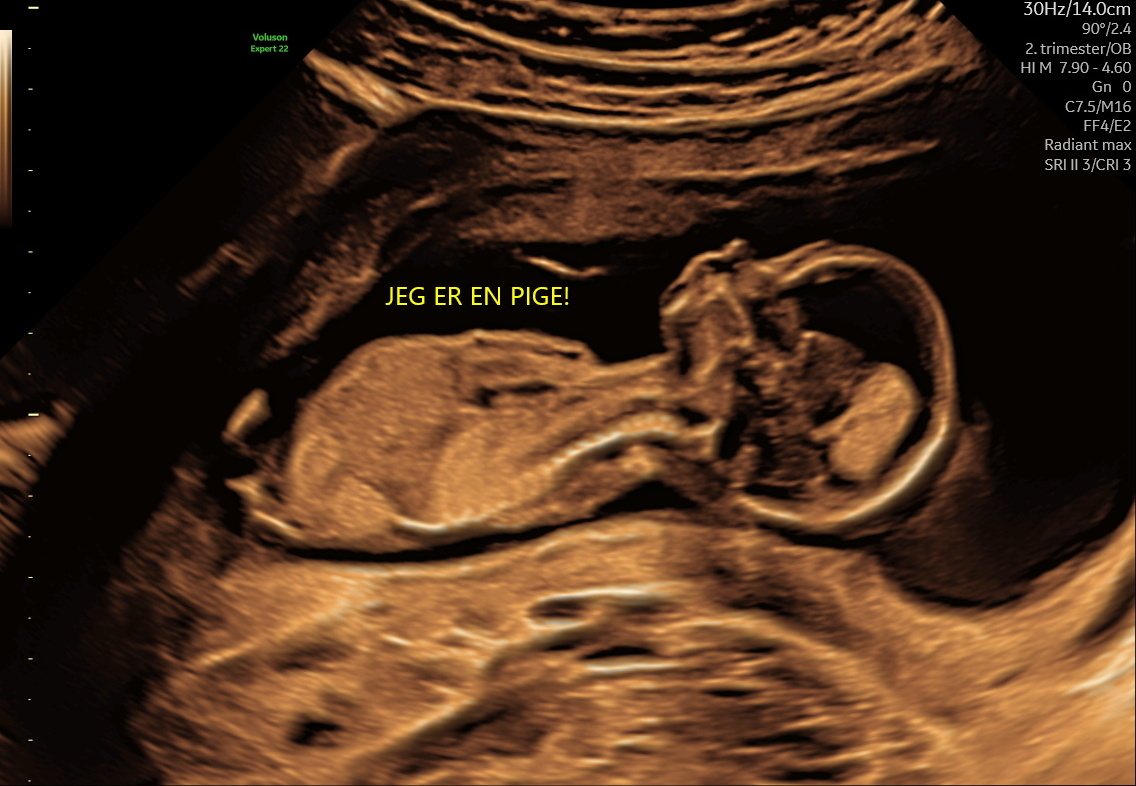

Kønscanning

Pige eller dreng fra uge 14+0

595 kr. / 495 kr. returkunde